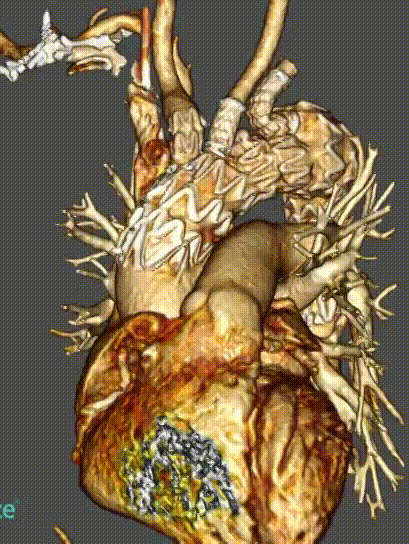

★ 病例5:解剖变异

(右位弓,迷走右锁骨下动脉)

释放方法和正常手术相同,但方向相反,需要调整。特别是分支的走向测试了该装置适应不同解剖结构的能力和便利性。

术后血管造影显示,所有分支方向与患者血管解剖结构匹配,尤其是无名动脉,外侧成近90°角,无内漏发生。随访显示所有分支通畅,无扭曲或迂曲,无卒中及内漏。